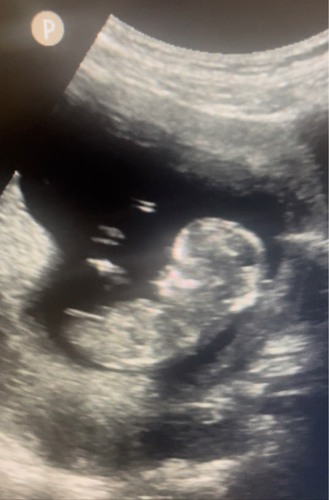

Ben benieuwd! ☺️ 12+4

Jongen denk ik